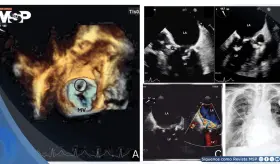

Paciente con marcapasos reciente desarrolló endocarditis infecciosa por Staphylococcus epidermidis complicada con pseudoaneurisma del intervalo mitral-aórtico y perforación valvular mitral.